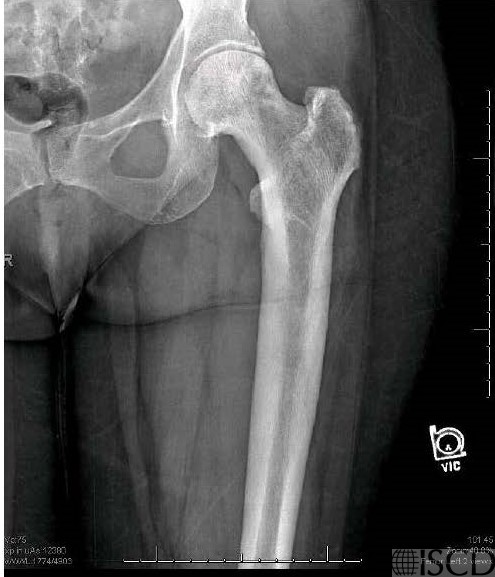

The corresponding radiograph in the left femur shows thickened trabeculations extending to the edge of the bone and thickened cortices extending to the middle of the shaft.